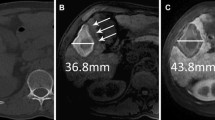

Images in a 69-year-old man with moderately differentiated hepatocellular carcinoma. At preablation MR imaging, the axial unenhanced T1-weighted image (A) shows an isointense tumor (black arrow), and axial (B) and coronal (C) hepatobiliary phase images show a hypointense tumor (black arrows). Tumor size is 18 mm, and TLCR on axial unenhanced T1-weighted and HBP imaging are 0.21 and 0.84. After radiofrequency ablation for the tumor, axial unenhanced T1-weighted imaging (D) shows a central hyperintense tumor and a broad hyperintense ablation margin (white arrow). This ablation margin is classified as indefinite. Axial (E) and coronal (F) hepatobiliary phase images show a central hypointense tumor with a marginal hypointensity band (white arrows). Ablation margin and hepatic parenchyma show similar intensity. This ablation margin is classified as visible. Using combined images, the status of the ablation margin is AM plus. During 20 months follow-up, there is no evidence of local tumor progression

Images in a 70-year-old woman with moderately differentiated hepatocellular carcinoma. At preablation MR imaging, the axial unenhanced T1-weighted image (A) shows a hypointense tumor (white arrow), and axial (B) and coronal (C) hepatobiliary phase images demonstrate a hypointense tumor (white arrows). Tumor size is 15 mm, and TLCR on axial unenhanced T1-weighted and HBP imaging are 0.13 and 0.48. After radiofrequency ablation for the tumor, axial unenhanced T1-weighted imaging (D) does not distinguish hyperintensity ablation margin from central hypointensity (black arrow). The ablation margin is indefinite. Axial hepatobiliary phase (E) shows a hypointensity ablation margin and a vague central tumor (black arrow), and coronal hepatobiliary phase image (F) shows a central hypointense tumor surrounded by a intermediate-intensity ablation margin (black arrows). Using combined images, the status of the ablation margin is AM plus. During 13 months follow-up, there is no evidence of local tumor progression